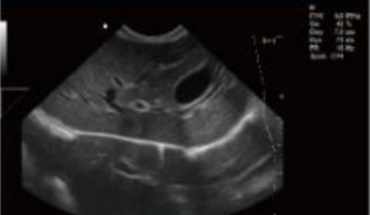

Rich Clinical Application Function

- Convex Extended Imaging Technology

- Linear Array Deflection/Trapezoidal Imaging Technology